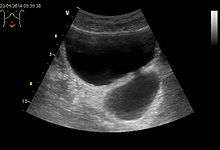

- Bladder diverticulum: Balloon-like growths on the bladder commonly associated with a chronic outflow obstruction, such as benign prostatic hyperplasia in older males. Usually found in pairs on opposite sides of the bladder, bladder diverticula are often surgically removed to prevent infection, rupture, or even cancer.